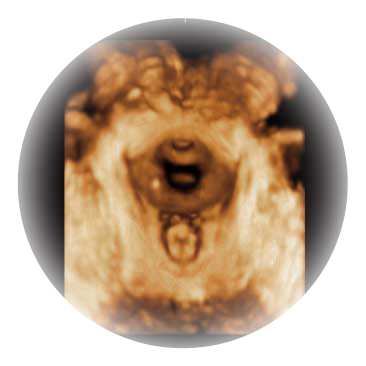

• M-Slice多切面成像

0.5mm厚度的薄层切片显像,可清晰显示微小病灶的连续断面。

• S-Live Silhouette光影成像

可同时显示组织结构表面和内部的轮廓信息,达到透视效果,为临床提供更丰富的诊断信息。